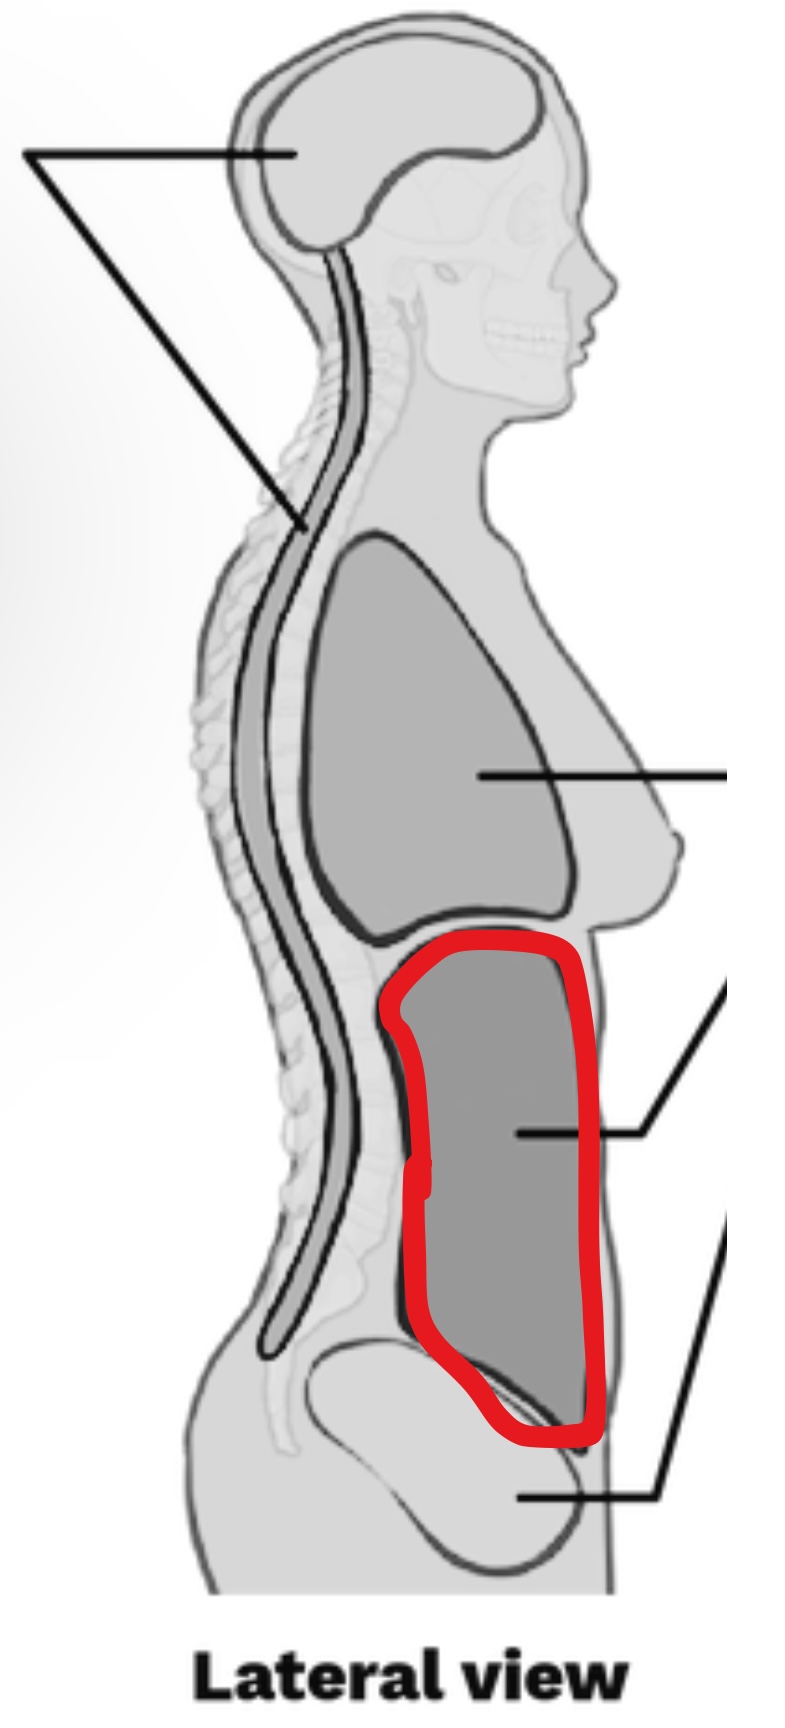

What cavity is this?

Ventral body cavity

What Cavity is this?

Thoracic cavity

What cavity is this?

Abdominopelvic Cavity